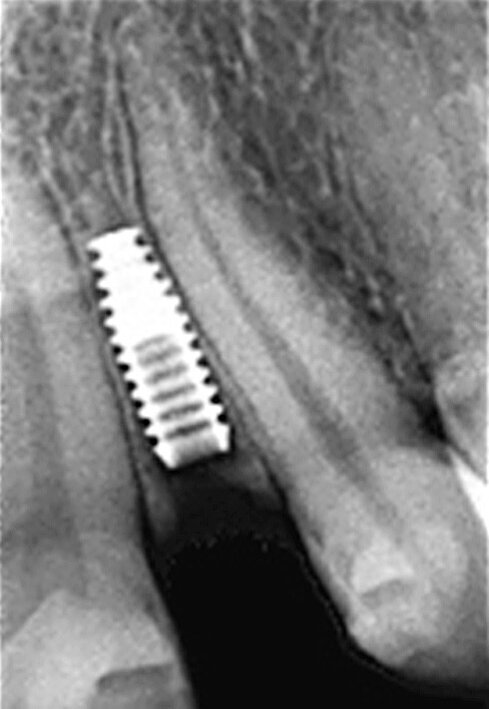

Fig. 8 : Radiographie de contrôle finale trois ans après la mise en fonction. Il faut noter le design de platform-switching entre le col de l’implant et la base hémisphérique du pilier.

L’implant a été mis en place au moyen d’un instrument spécial pour l’insertion d’implant, qui permet au praticien de pousser l’implant fermement, en appliquant une pression précise dans l’ostéotomie (Fig. 5). La dernière étape a consisté à introduire complètement l’implant au moyen du maillet, et de l’instrument d’insertion fixé à la poignée de serrage droite. L’implant étroit était dès lors bien positionné entre les deux racines (Fig. 6). L’implant de 8 mm de long et de Ø 3 mm a été inséré par l’application d’une pression dans l’ostéotomie, et l’utilisation du maillet et de l’instrument d’insertion à 3 mm sous le niveau de l’os crestal (Fig. 7). La seconde phase du traitement a été réalisée après six mois de cicatrisation et a consisté à désenfouir l’implant. Un pilier ayant un corps de Ø 2 mm et une base hémisphérique de Ø 4 mm a été choisi pour connecter les couronnes provisoires à l’implant. Il est important de veiller à la bonne cicatrisation du tissu mou autour du contour coronaire adéquat, et celle-ci peut être obtenue par une modification du profil d’émergence de la couronne provisoire jusqu’à la formation des papilles. Après la cicatrisation complète du tissu mou, la dernière empreinte a été prise et la couronne définitive a été scellée sur le pilier en titane (Figs. 8 et 9).